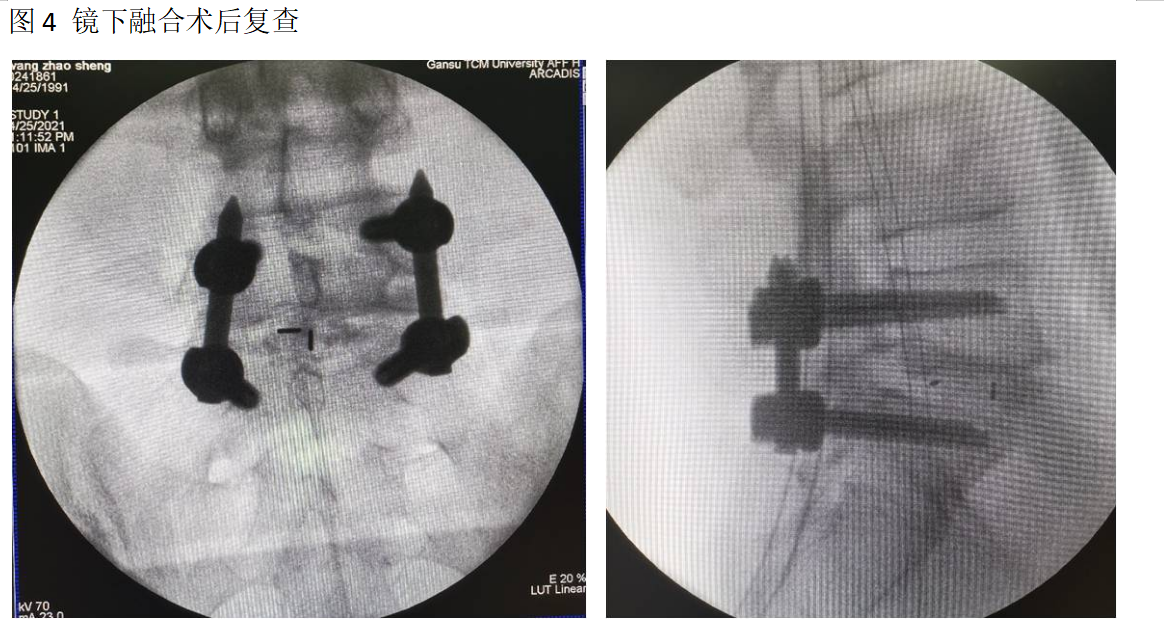

随着脊柱内镜全可视技术的完善,及磁导航技术的指导,使得镜下融合技术手术时间大大缩短。